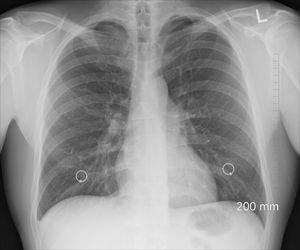

Die Diagnose einer Lungenfibrose erfolgt in der Regel durch eine Kombination aus Anamnese, körperlicher Untersuchung, bildgebenden Verfahren wie Röntgenaufnahmen oder Computertomographie (CT) sowie Lungenfunktionstests. Eine genaue Diagnosestellung ist wichtig, da es über 200 verschiedene Lungenerkrankungen gibt, die unter den Begriff der Lungenfibrose fallen können. Zudem müssen andere Erkrankungen mit ähnlichen Symptomen wie COPD oder Herzinsuffizienz ausgeschlossen werden.